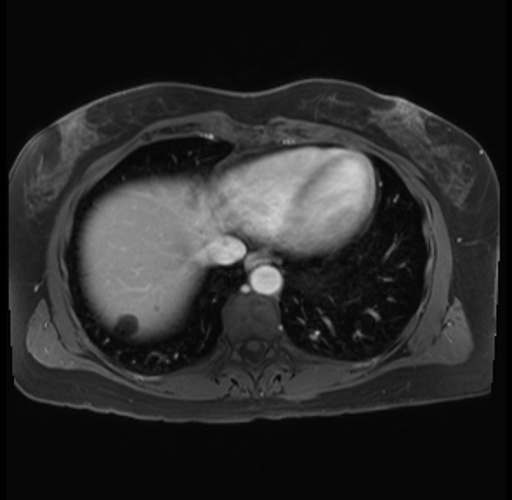

Imaging Analysis

Look through the patient's CT scan to identify any areas of concern for the necessary procedure.

Based on your CT findings, which issue(s) are present and would give reason for "planned slowing down moment(s)" in this case?